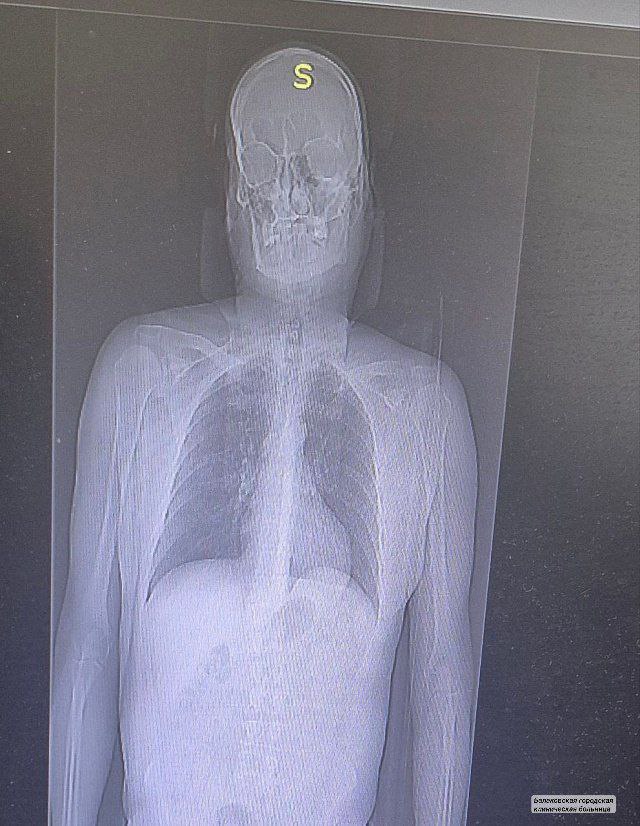

Итог «путешествия»: переломы двух ребер и ушибы. Медики стабилизировали состояние любителя селфи. Сразу после госпитализации пациенту была оказана необходимая медицинская помощь, включая обезболивание и рентгенографию для уточнения характера травм. Врачи отметили, что, несмотря на падение с высоты, состояние пострадавшего оценивается как удовлетворительное. Ему предстоит пройти курс реабилитации. Уже на следующей неделе его обещают выписать. Врачи также подчеркнули важность соблюдения техники безопасности при посещении подобных объектов.